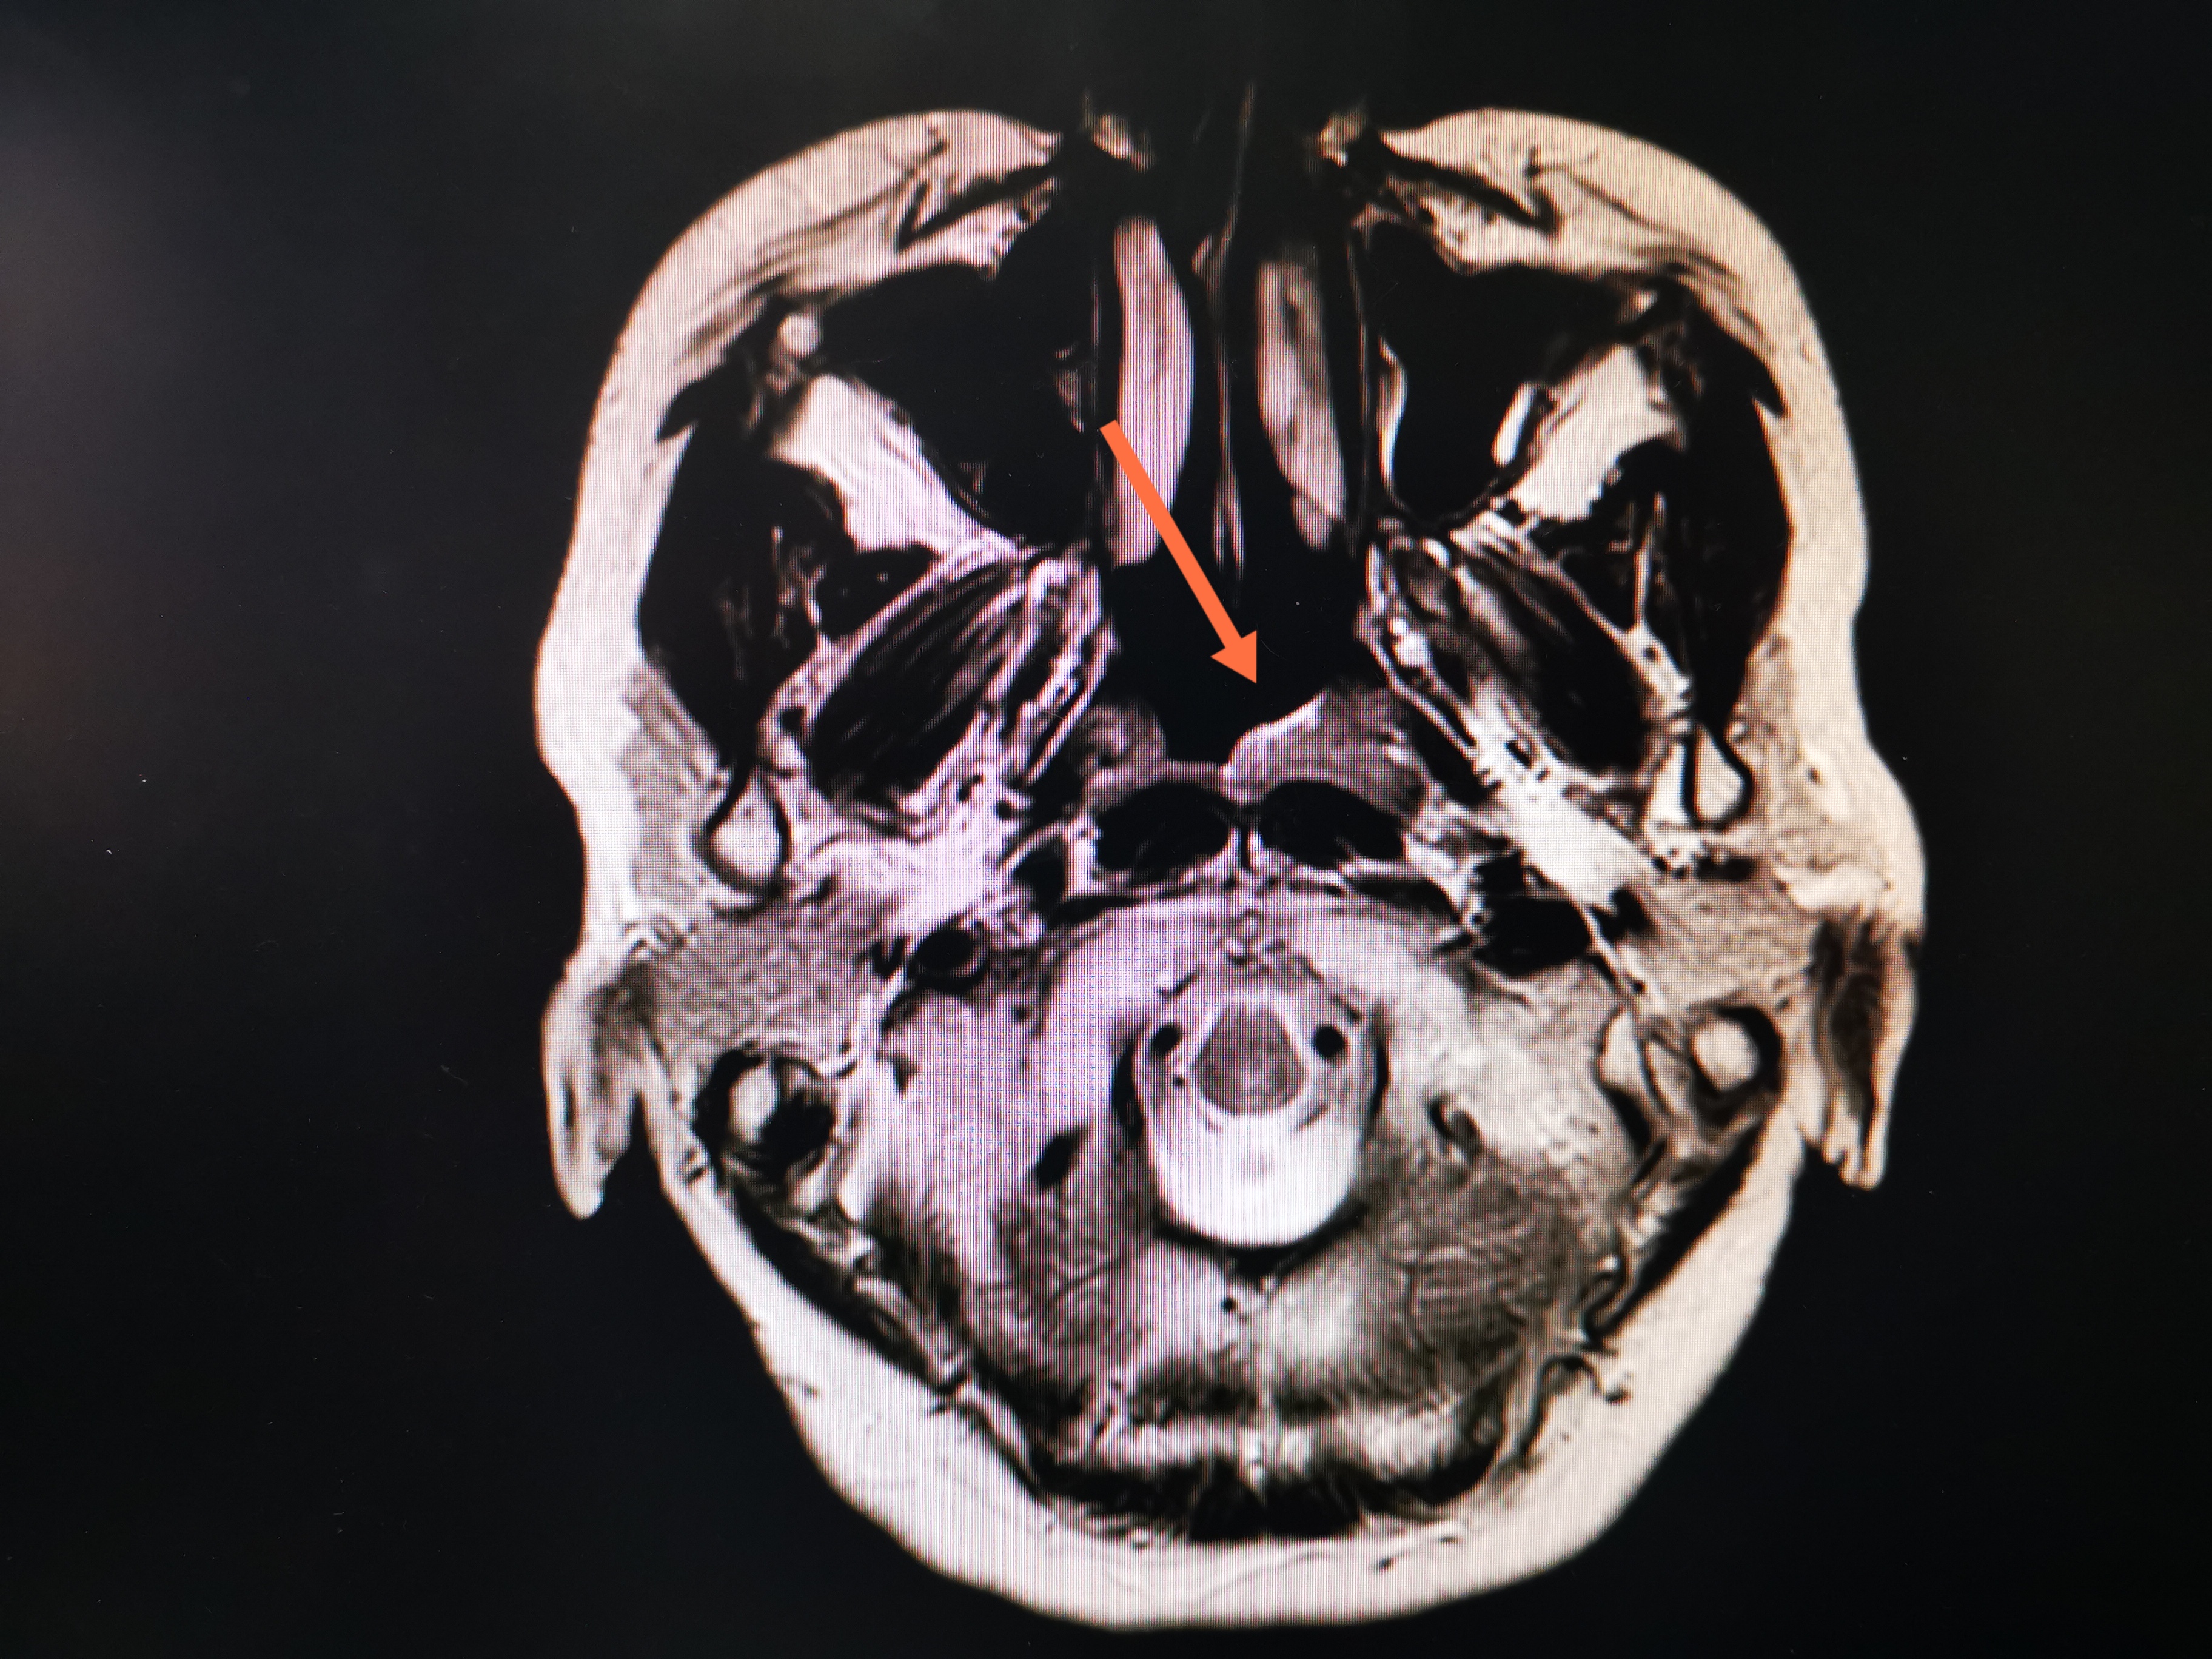

MRI红箭头示肿瘤所在位置